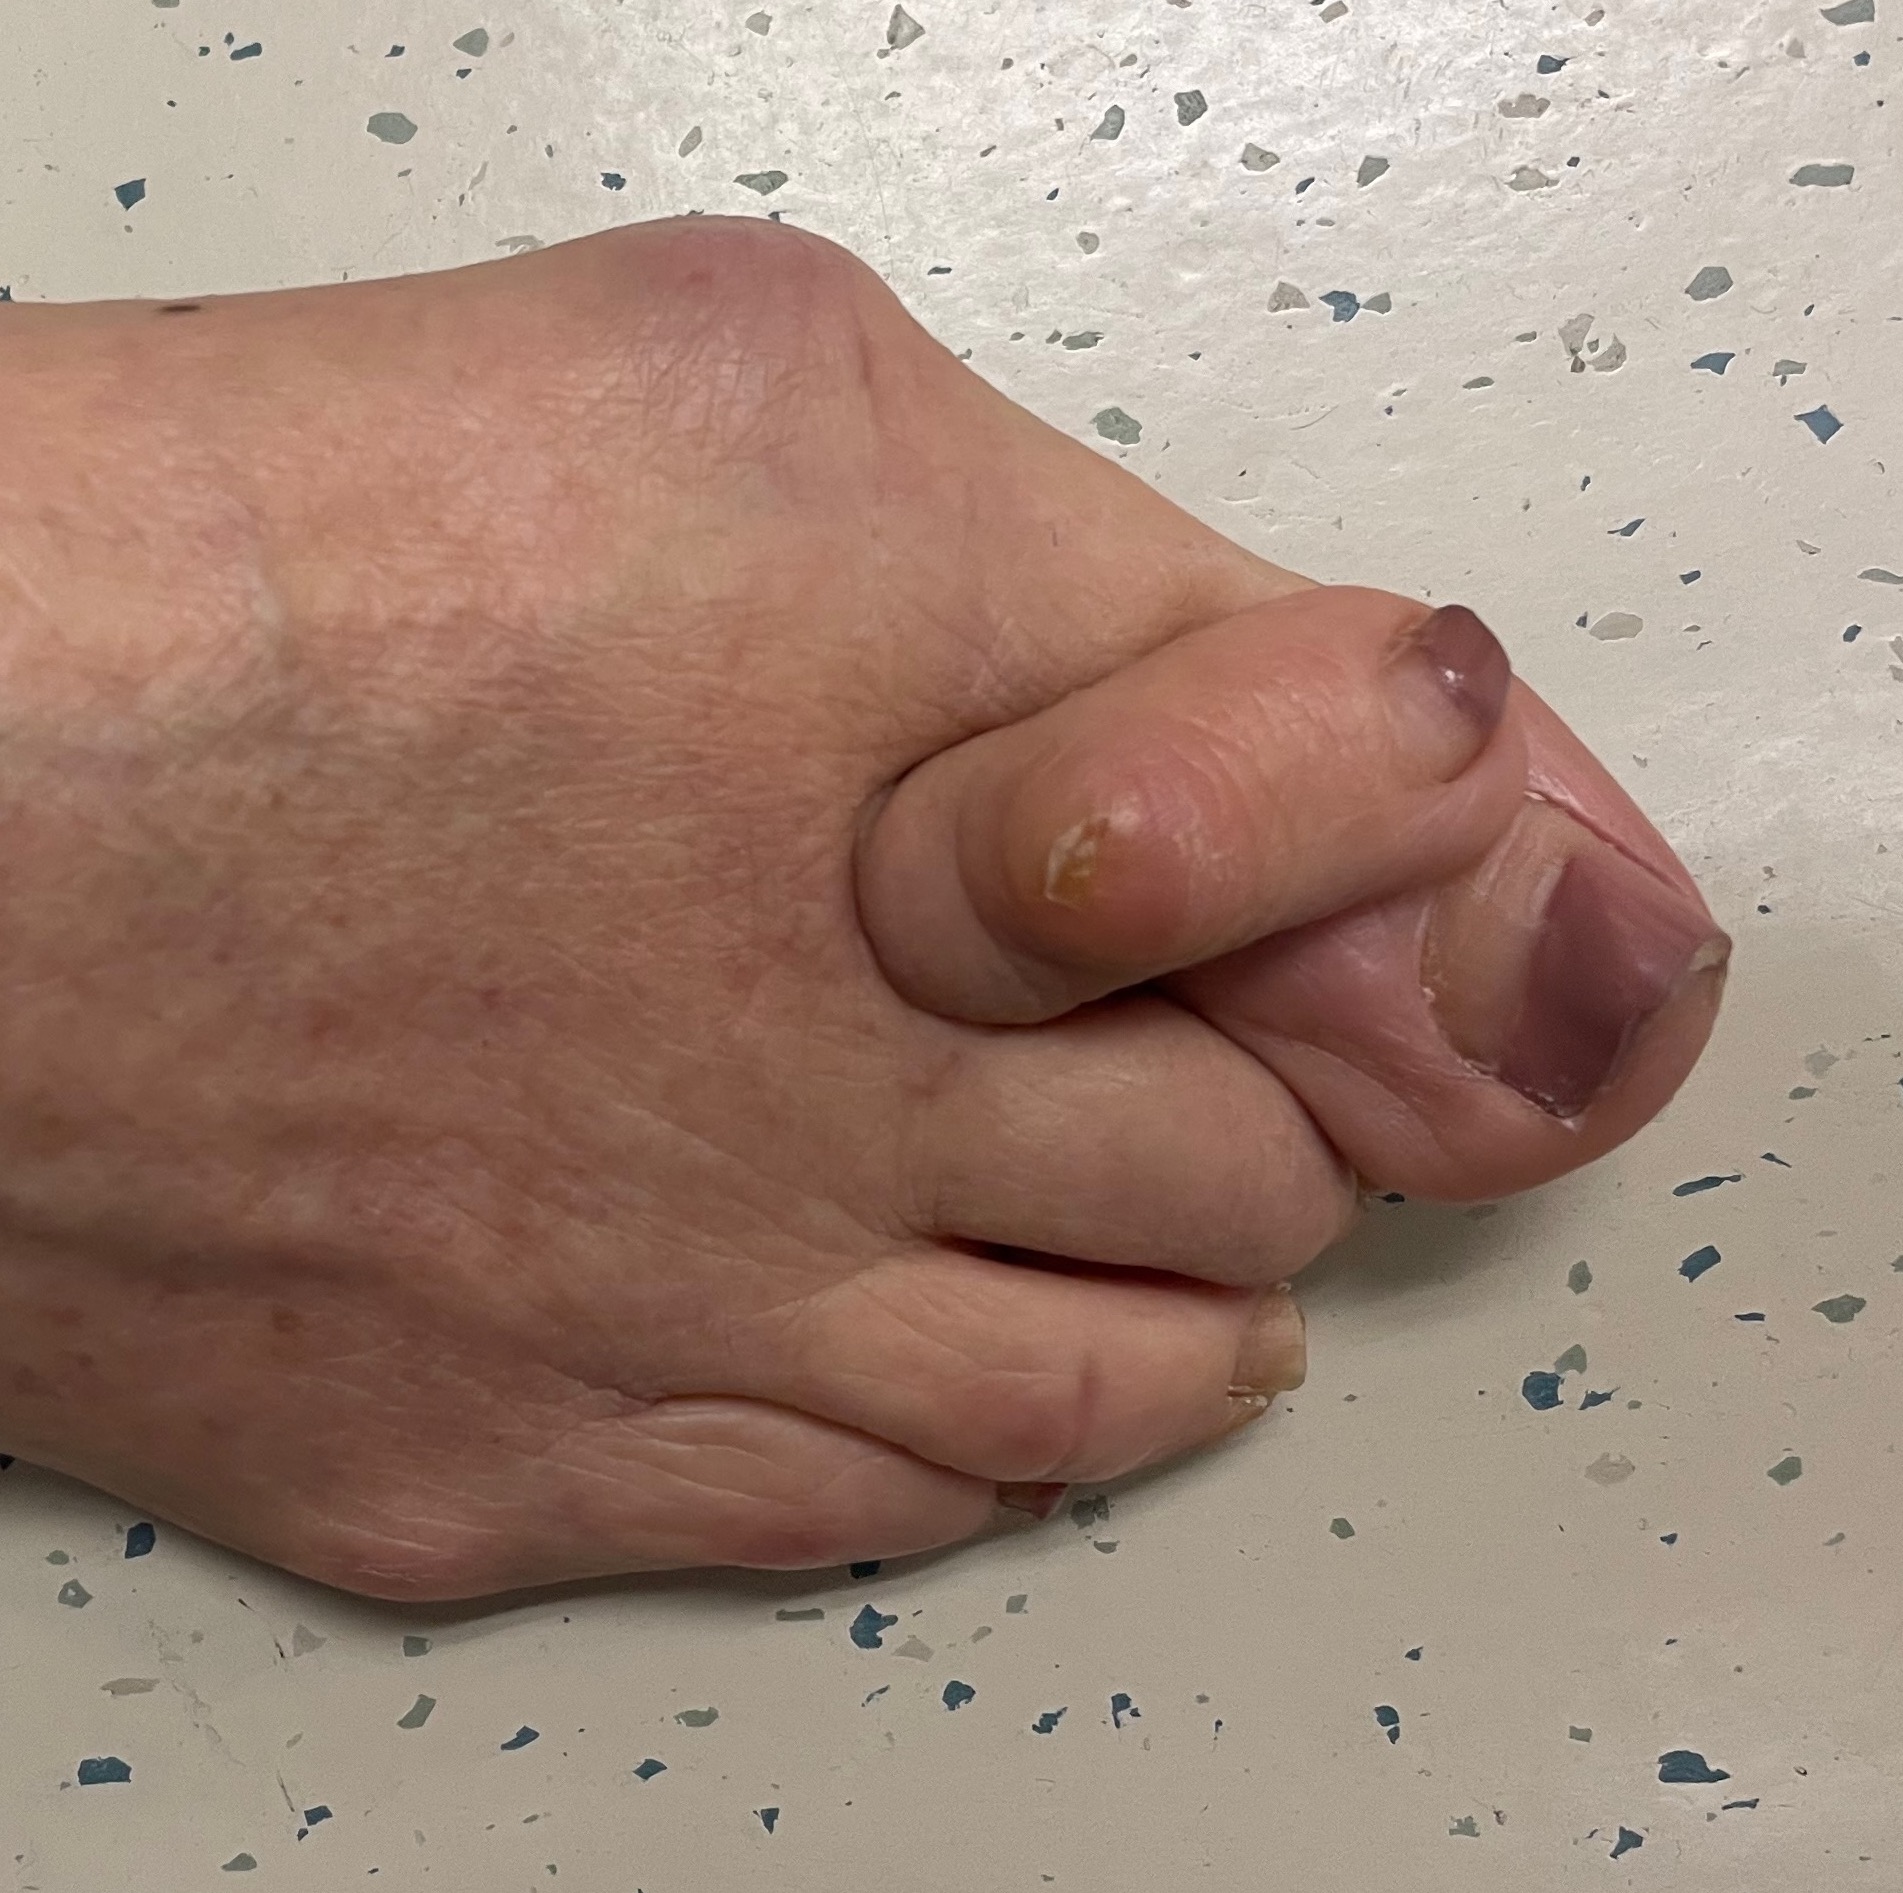

Curly toe

Definition

Under-riding toe

- toe lies beneath adjacent toe

- congenital deformity